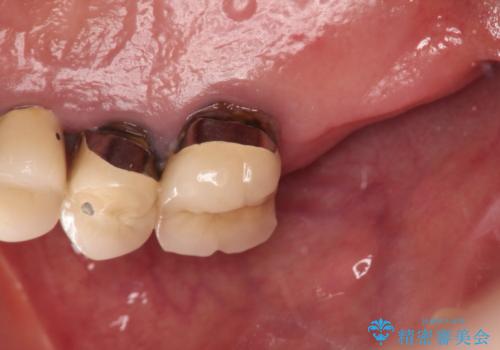

- 噛むと右の奥歯が痛い、何度も腫れを繰り返すとの事で来院された患者様です。

上顎は歯根破折と排膿が認められ、下顎も骨吸収により残せる状態ではないと判断し、抜歯後にインプラント治療(右上567、右下67)を行うことになりました。